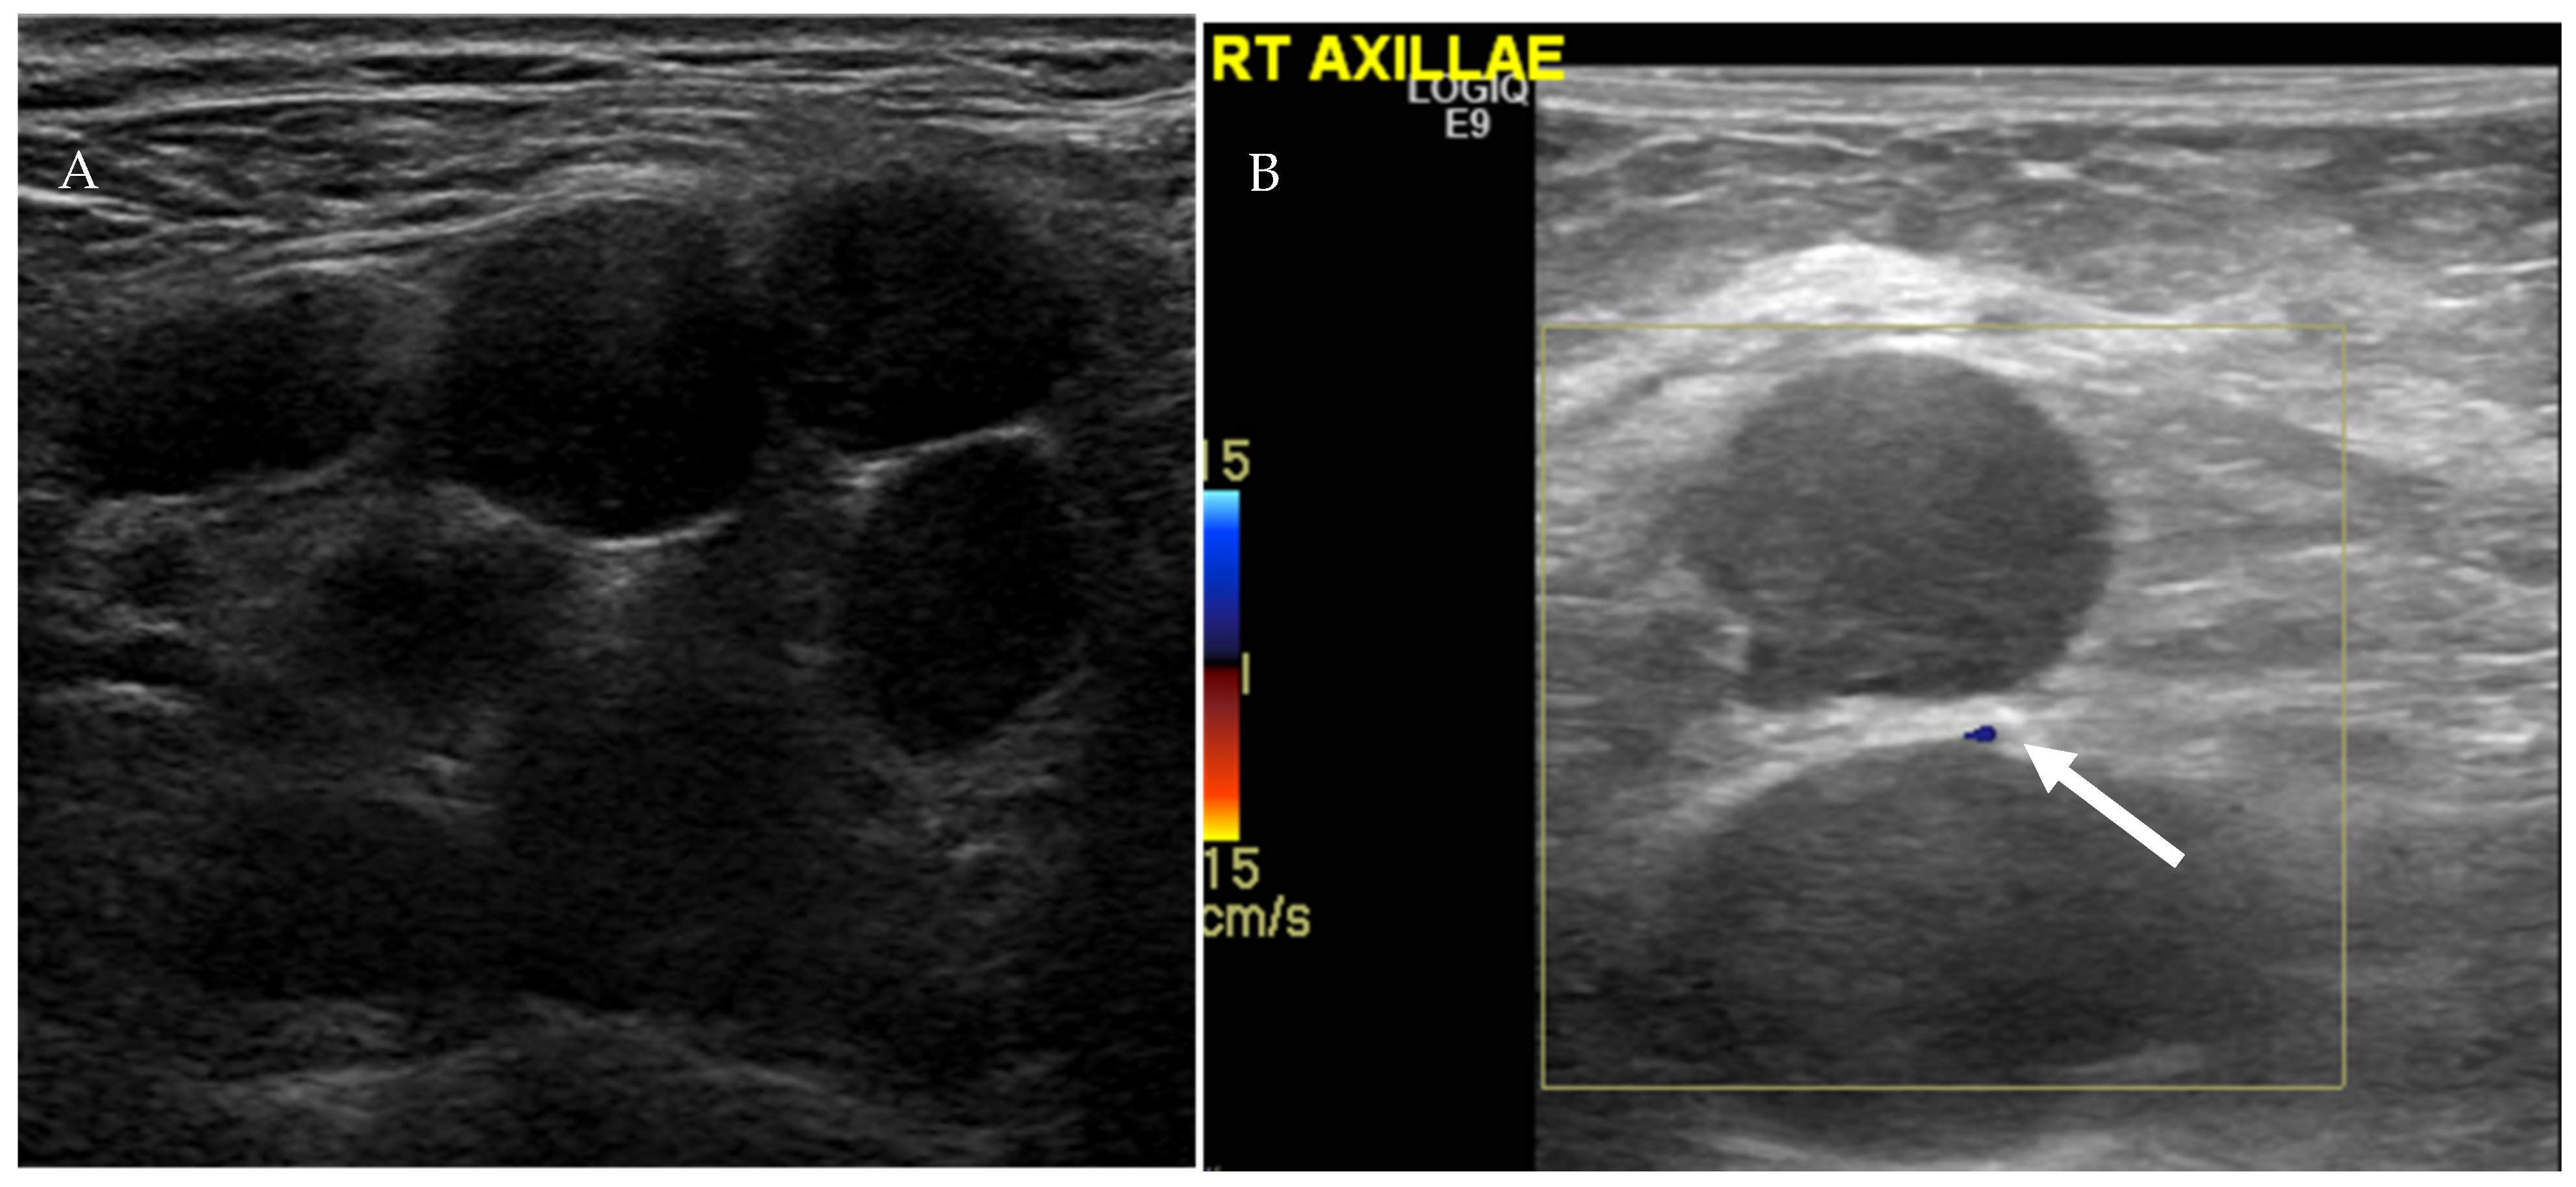

4.1.1. Ultrasound Evaluation of the Lymphatic System

| US Criteria | Benign Lymph Node | Malignant Lymph Node |

|---|---|---|

| Size | <1 cm in short axis | ≥1 cm in short axis |

| Shape | Oval or elliptical | Round |

| Border | Indistinct | Sharp |

| Echogenicity | Hypoechoic | Very hypoechoic |

| Hilum | Maintained fatty hilum | Absent fatty hilum |

| Vascularity | Avascular or hilar vascularity | Peripheral or mixed |

| Resistive index | Low | High |